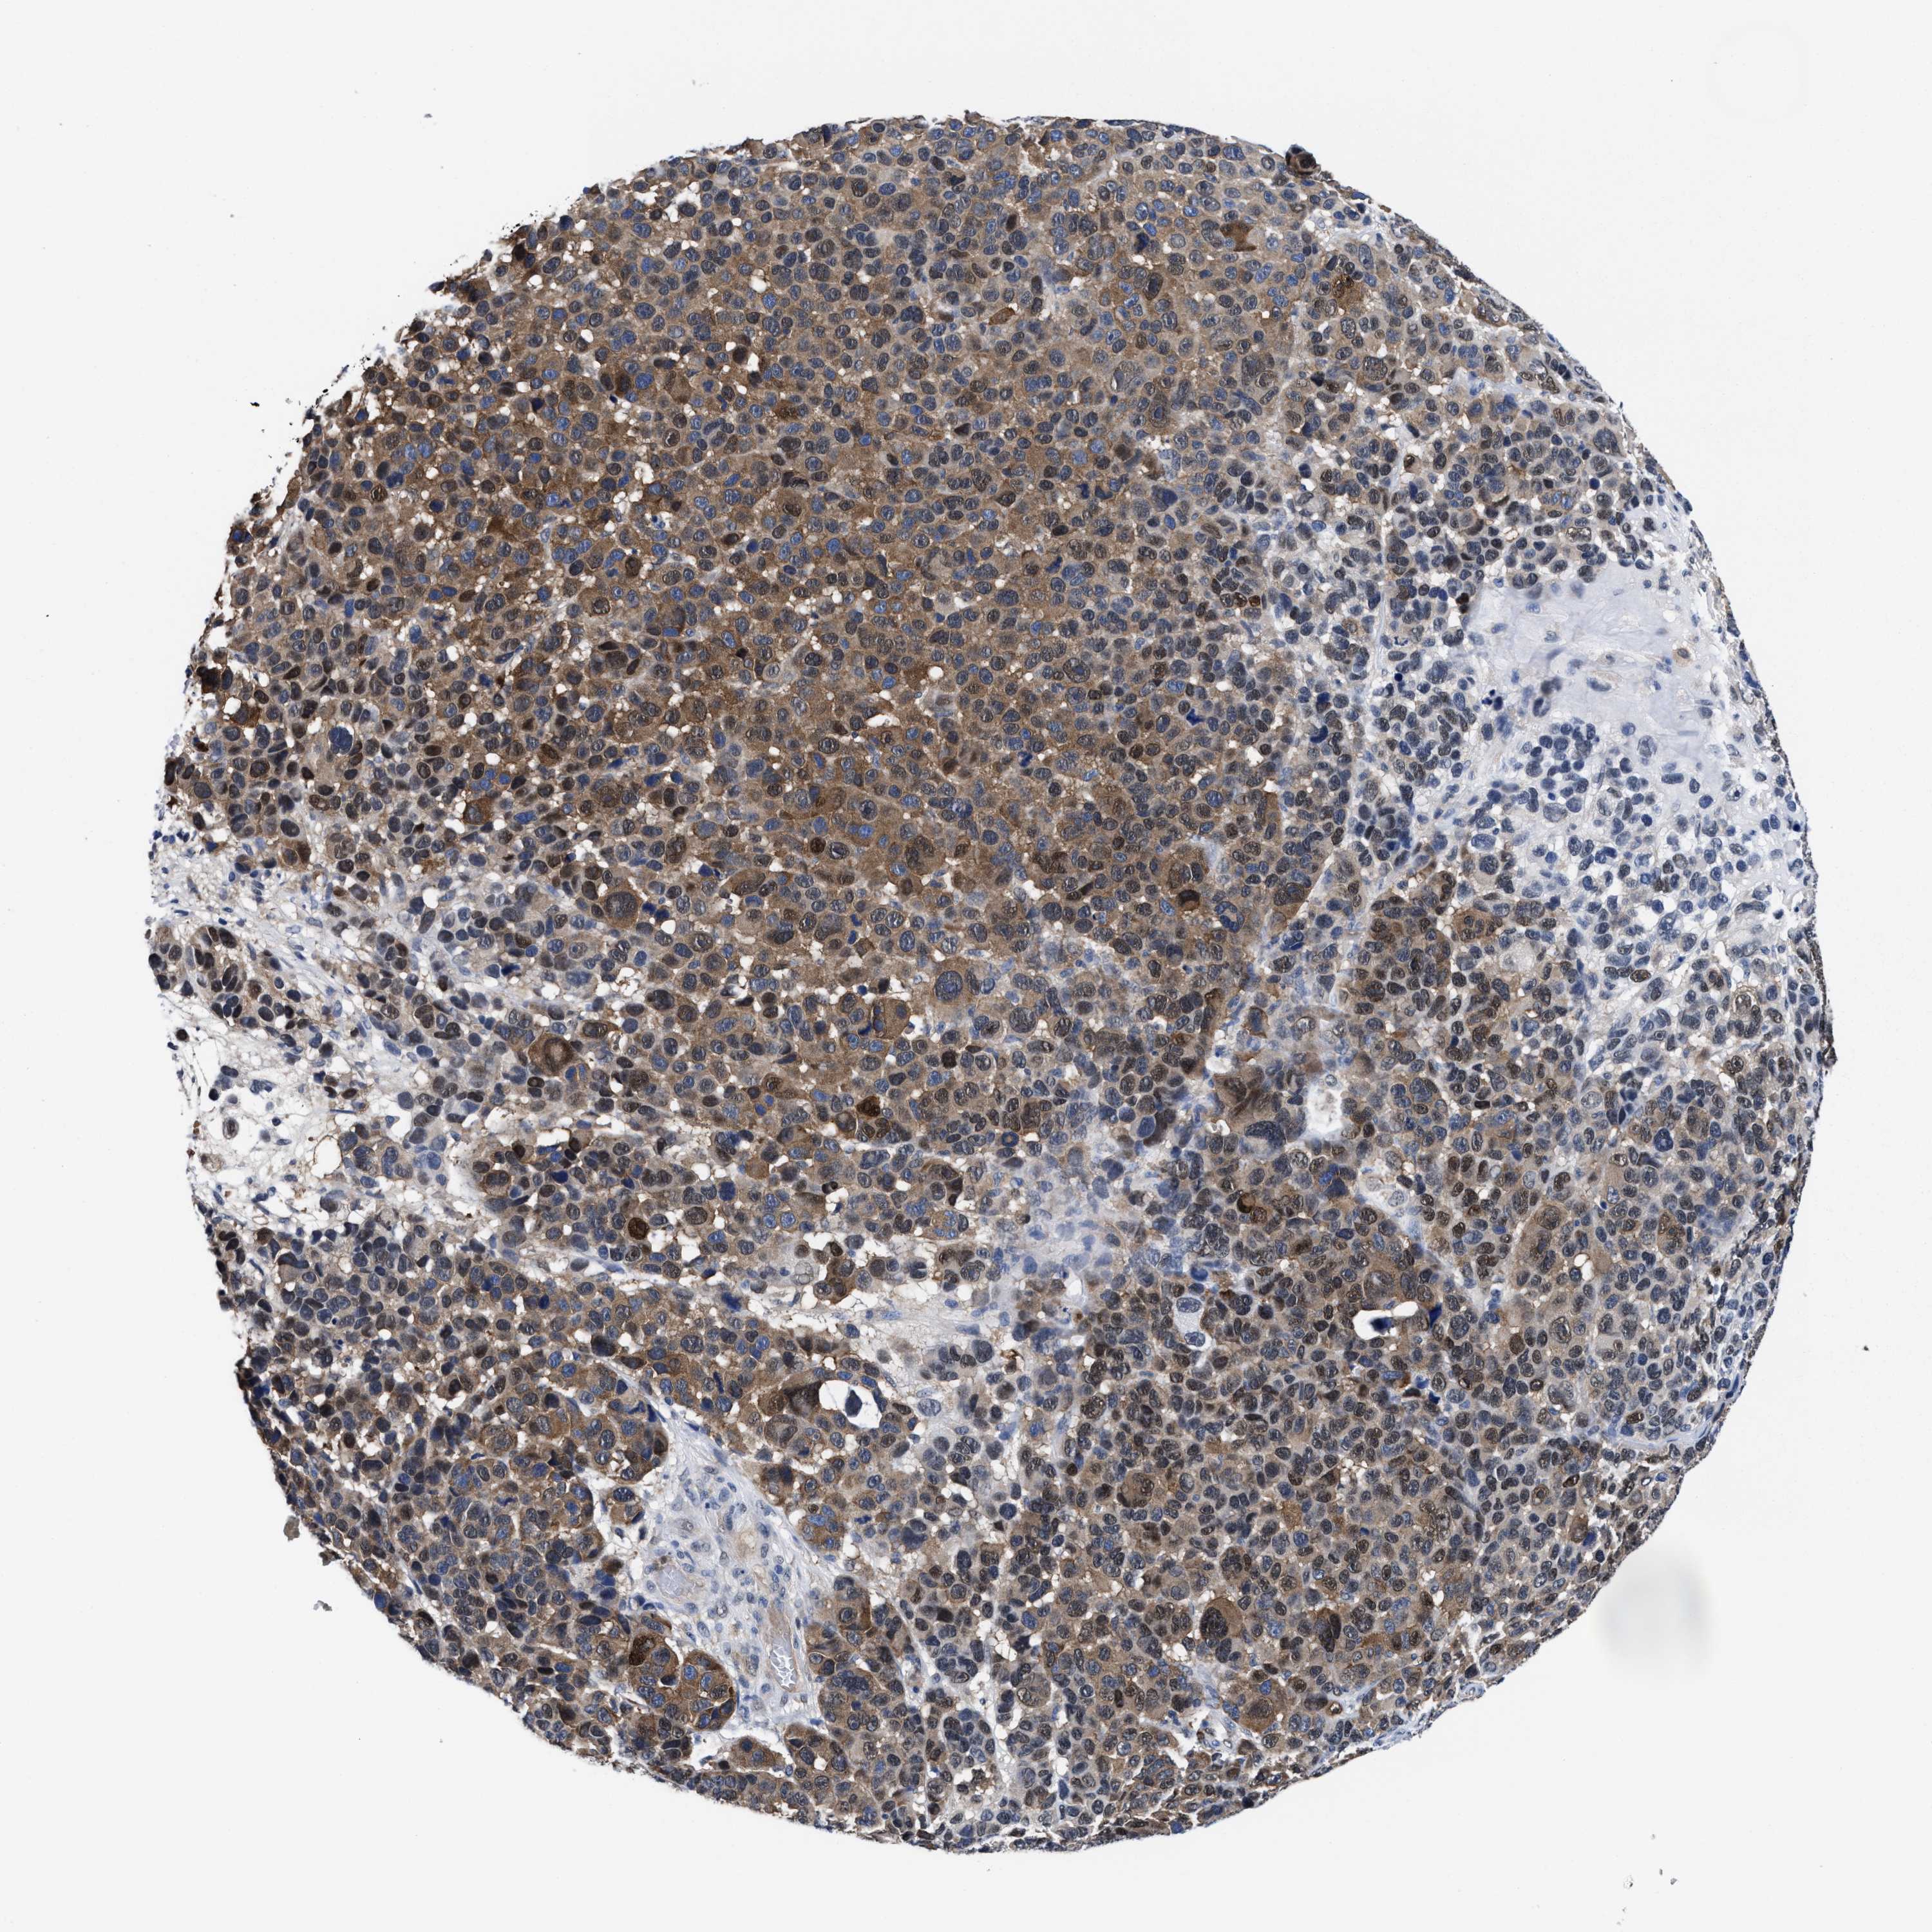

MELANOMA - Protein expressioni

A mouse-over function shows sample information and annotation data. Click on an image to view it in a full screen mode. Samples can be filtered based on level of antibody staining by selecting one or several of the following categories: high, medium, low and not detected. The assay and annotation is described here.

Note that samples used for immunohistochemistry by the Human Protein Atlas do not correspond to samples in the TCGA dataset.

Antibody stainingi

Antibody staining in the annotated cell types in the current human tissue is reported as not detected, low, medium, or high, based on conventional immunohistochemistry profiling in selected tissues. This score is based on the combination of the staining intensity and fraction of stained cells.

Each image is clickable and will lead to virtual microscopy that enables deeper exploration of all samples and also displays staining intensity scores, fraction scores and subcellular localization as well as patient and tissue information for each sample.

HPA022434

HPA022953

HPA022959

HPA028758

CAB007783

Malignant melanoma, NOS

Malignant melanoma, Metastatic site